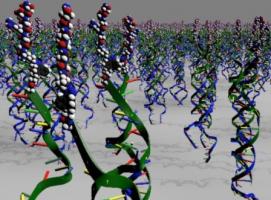

THÉRAPIE CELLULAIRE : Le matériau qui rétablit une signalisation cellulaire dynamique

Actualité publiée le 21/07/2017MÉDECINE RÉGÉNÉRATIVE: Rallonger les télomères pour rallonger la vie?